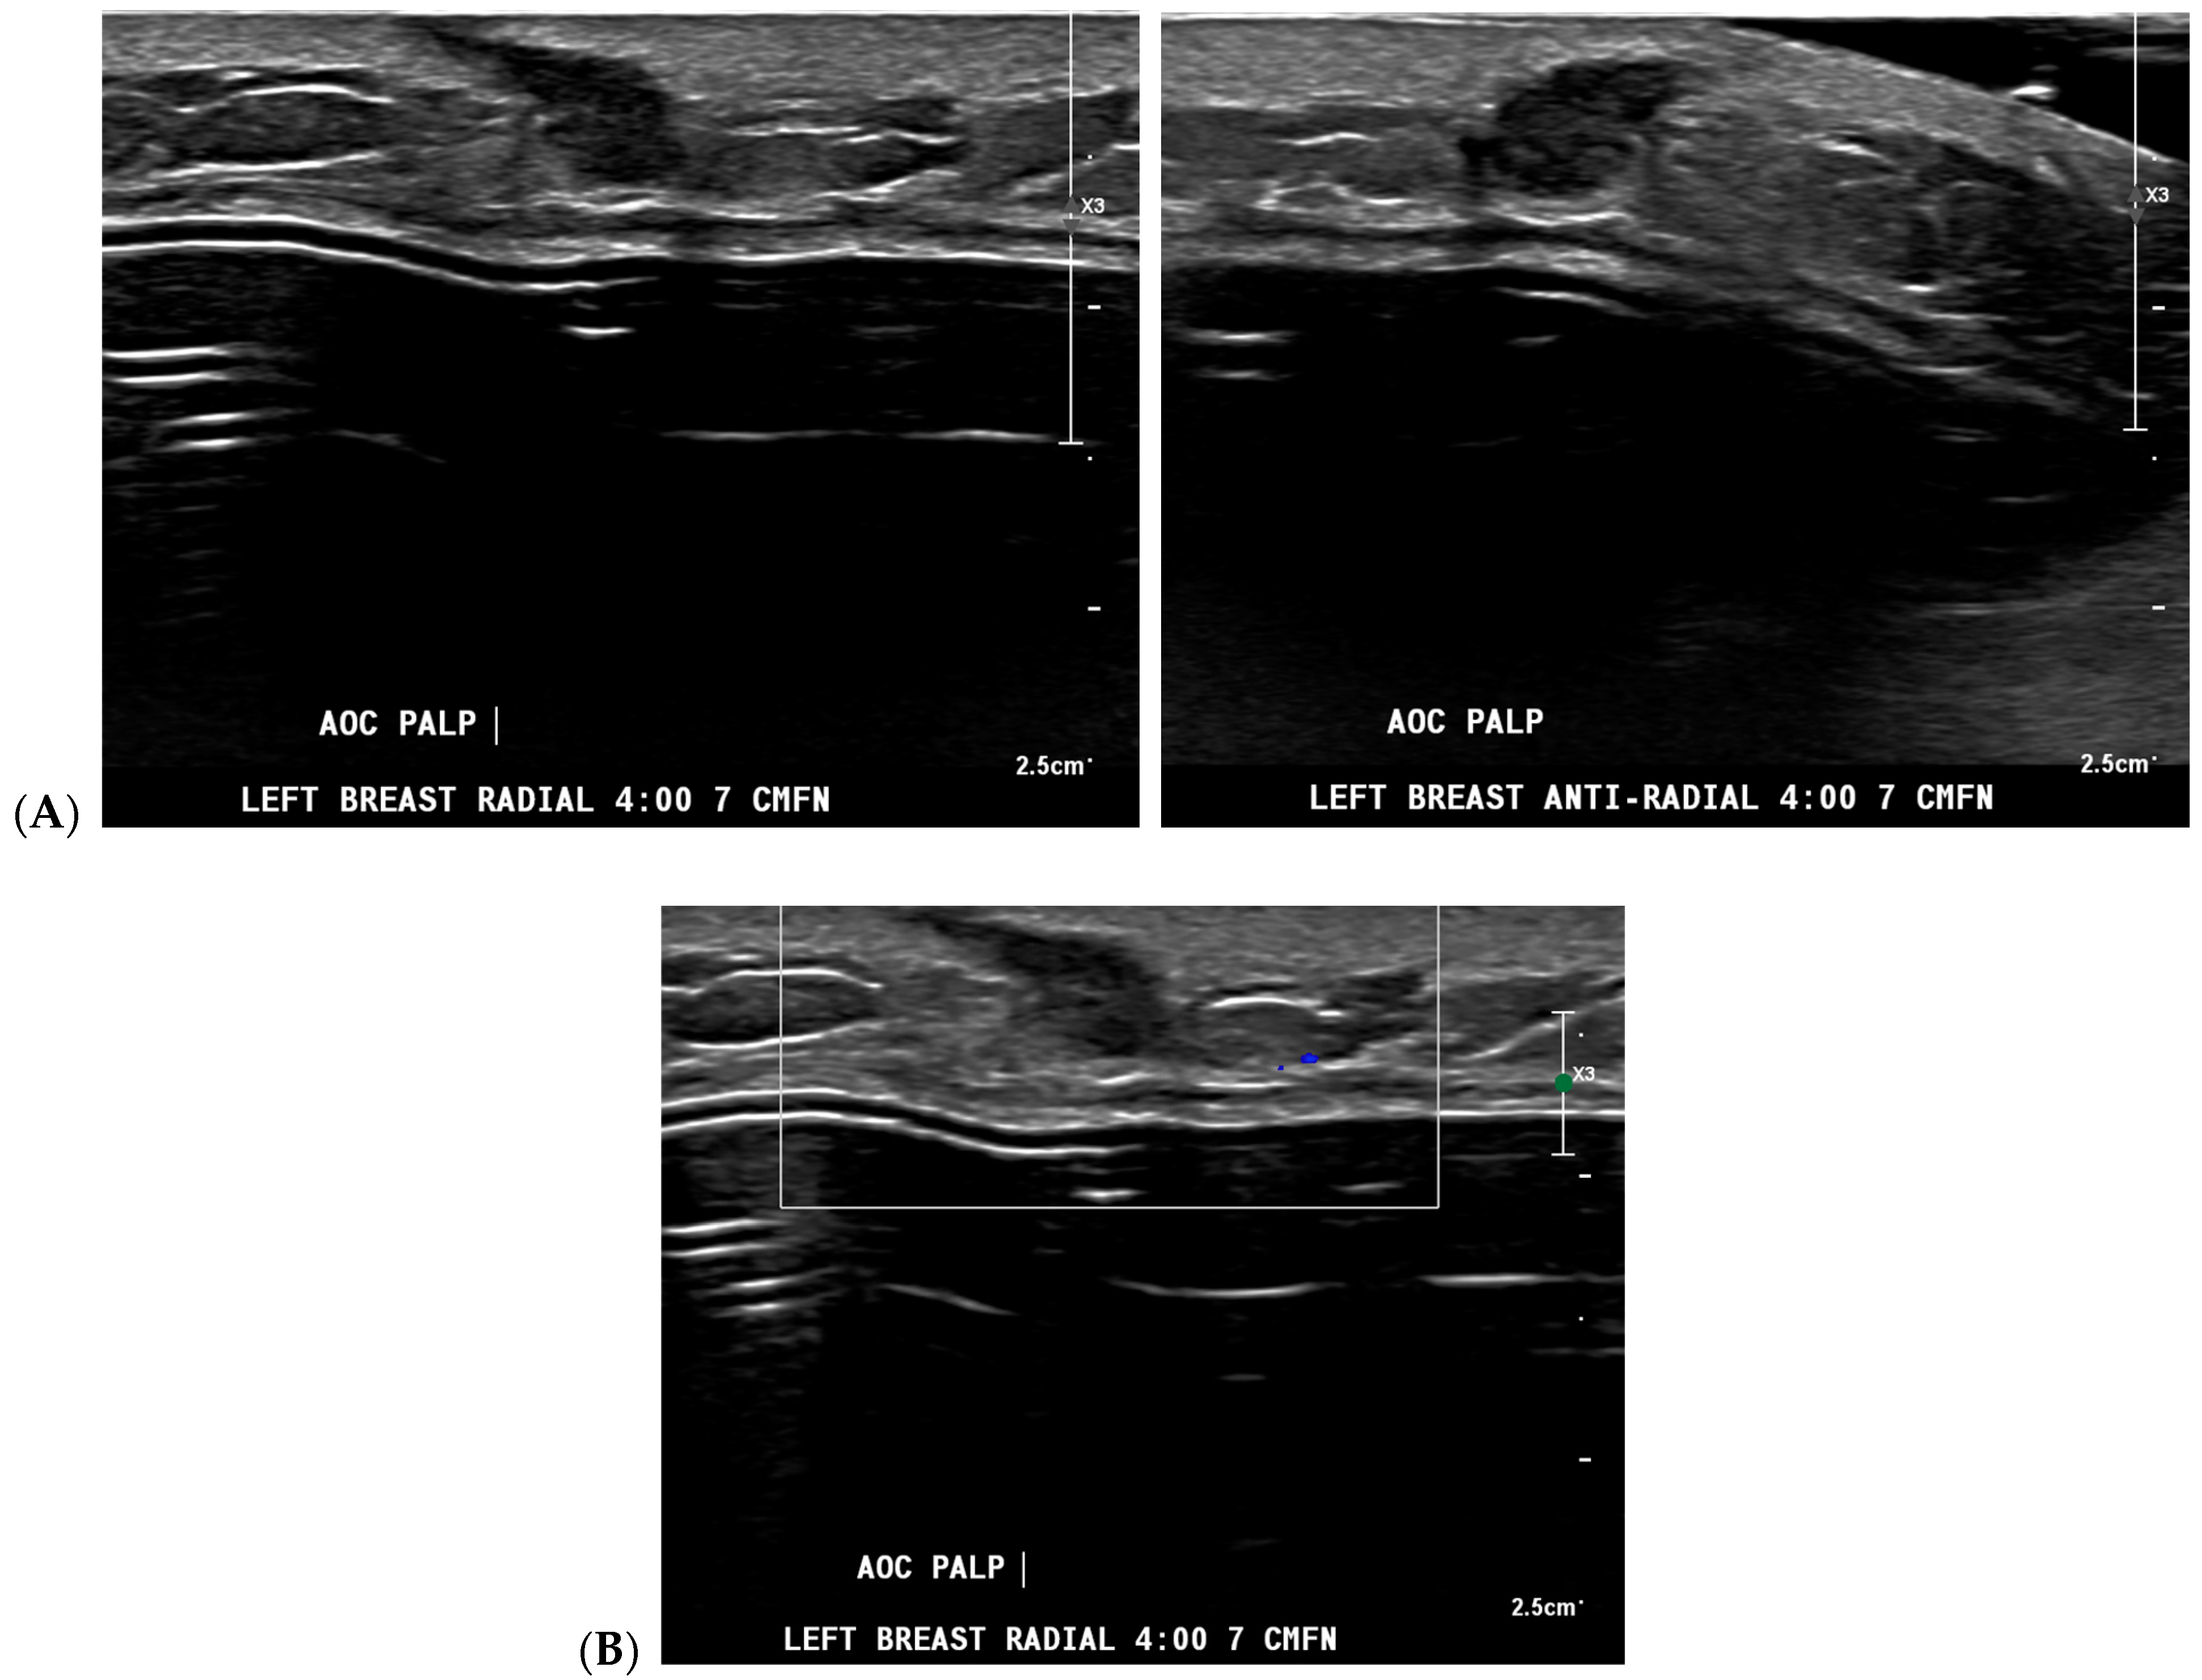

Cancer detection systems typically involve neural networks, machine learning, or deep learning developed from training models to recognize patterns, while diagnostic systems use an additional algorithm to classify [17]. Several CNN models have been developed to correlate ultrasound imaging features of a lesion with the four-classification breast cancer molecular subtypes [42]. Our institution uses Koios, which utilizes machine learning and AI to generate the probability of malignancy of a breast finding by evaluating a region of interest (ROI) selected by a radiologist [3,5]. Ultrasound AI has been found to reduce intra- and interobserver variability and to improve accurate BI-RADS classification of sonographic breast findings [3,5]. Ultrasound AI can also increase CDR [5] and reduce the number of unnecessary biopsies [5,43,44] (Figure 1, Figure 3, and Figure 4).

Figure 3.

A new cancer diagnosis appropriately classified as “malignant” by artificial intelligence (AI): This patient in her 40s with a history of left breast carcinoma diagnosed 1 year prior, status post-left mastectomy with chemotherapy and hormonal therapy, presented with a palpable abnormality in the superficial lower outer left breast. No new or suspicious findings were seen on the patient’s diagnostic mammogram. Correlating with the patient’s concern about a palpable lump, diagnostic ultrasound revealed an irregularly shaped, hypoechoic mass with angular margins that are non-parallel (A), and Doppler shows no vascularity (B). The AI program Koios recognized this mass as “Probably Malignant” (C). This was returned as biopsy-proven invasive ductal carcinoma. Images obtained from the Icahn School of Medicine at Mount Sinai.

Figure 4.

A benign finding appropriately classified as benign by artificial intelligence (AI): The patient initially presented for a bilateral screening mammogram and a bilateral screening breast ultrasound. A mammogram revealed benign dystrophic calcifications in the upper outer quadrant of the right breast (A). Correlating with findings on the mammogram, ultrasound revealed a complicated cyst showing posterior acoustic shadowing consistent with fat necrosis (B). The AI program Koios recognized this mass as “Benign” (C). Images obtained from the Icahn School of Medicine at Mount Sinai.